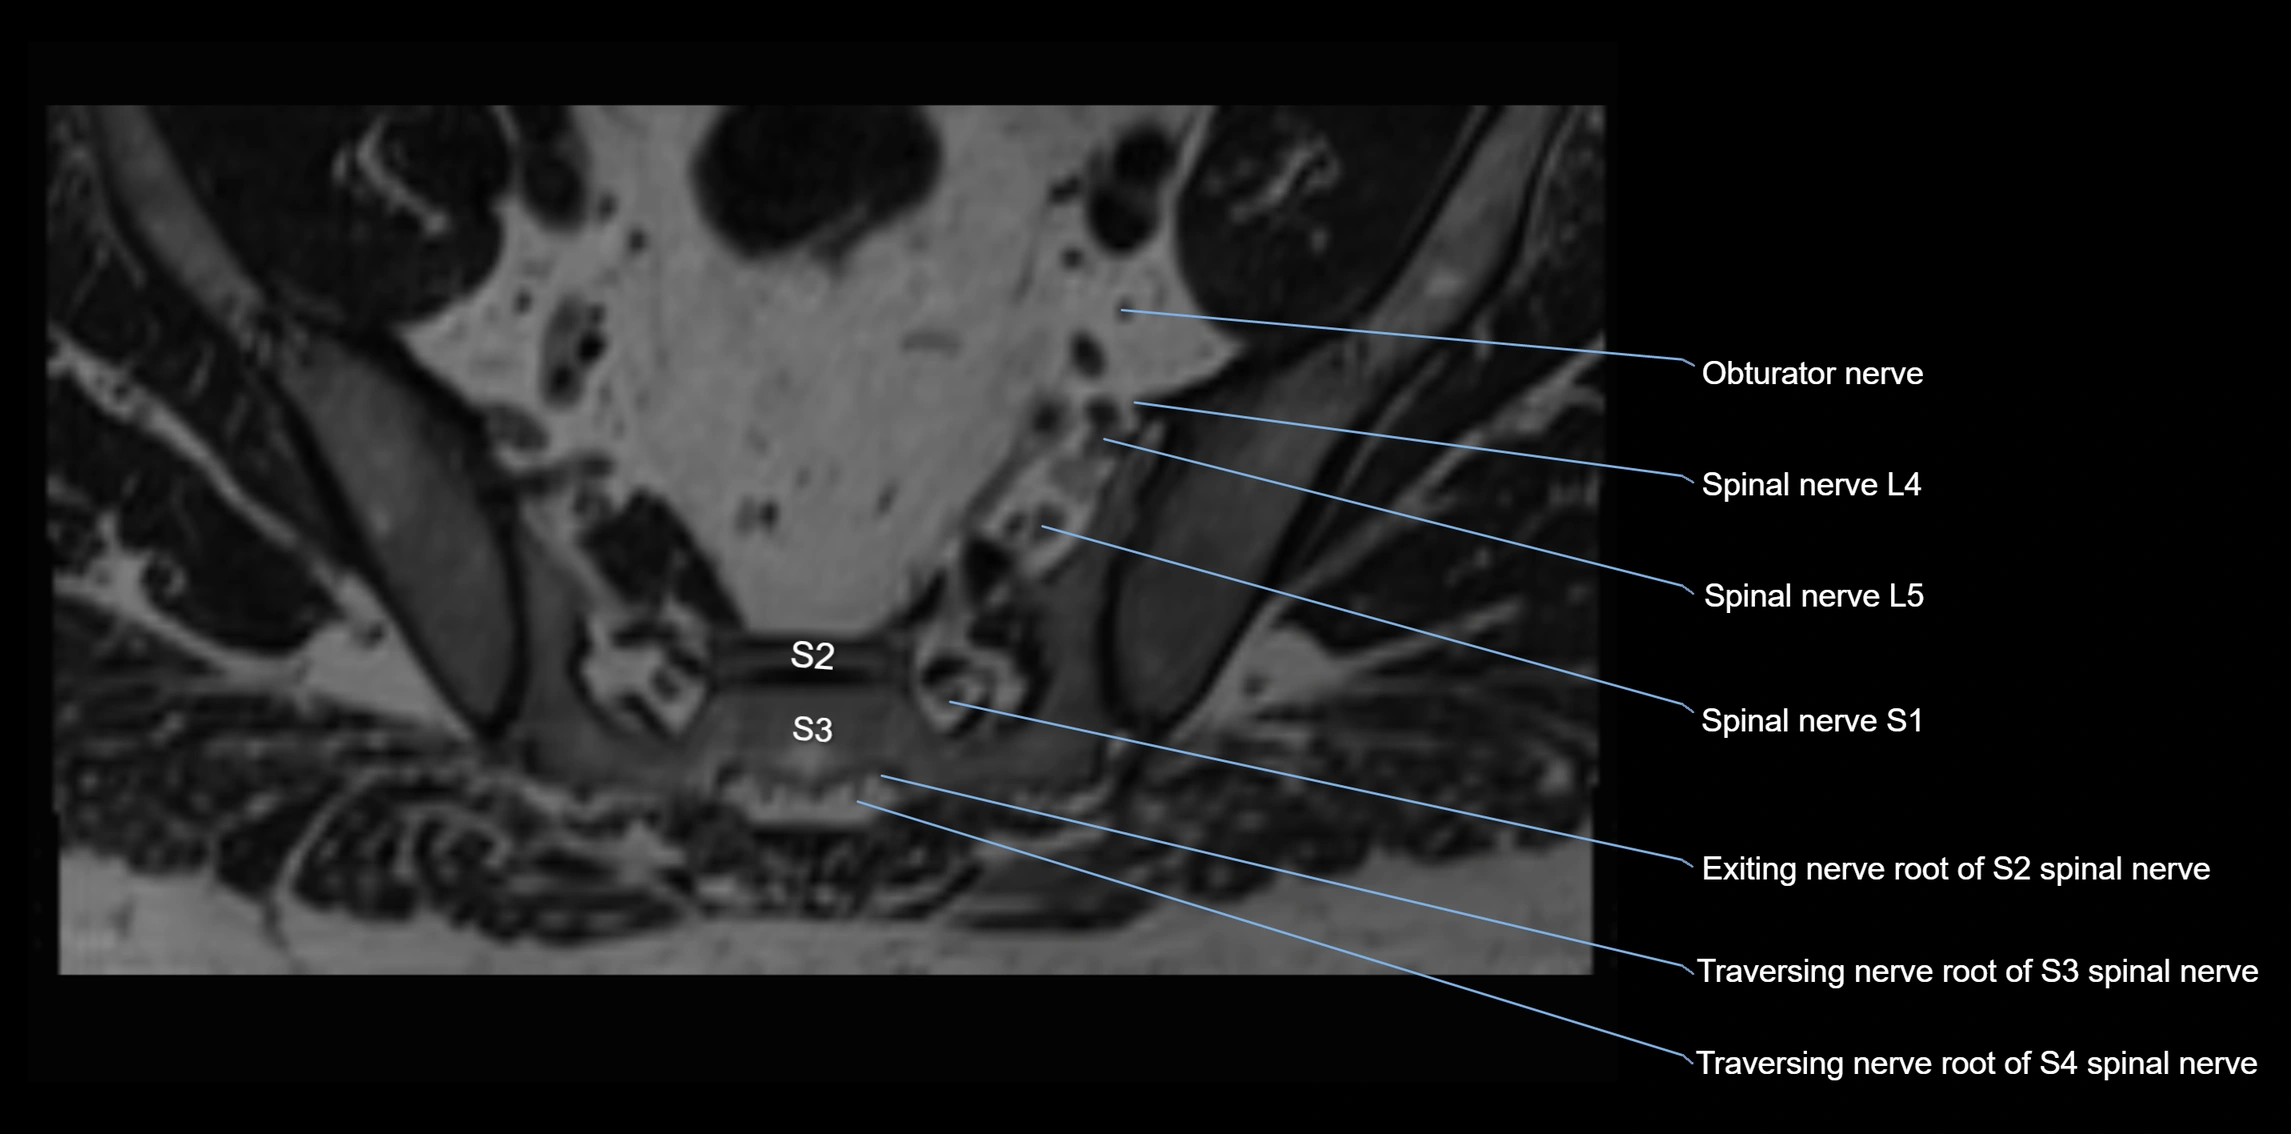

MRI image

image